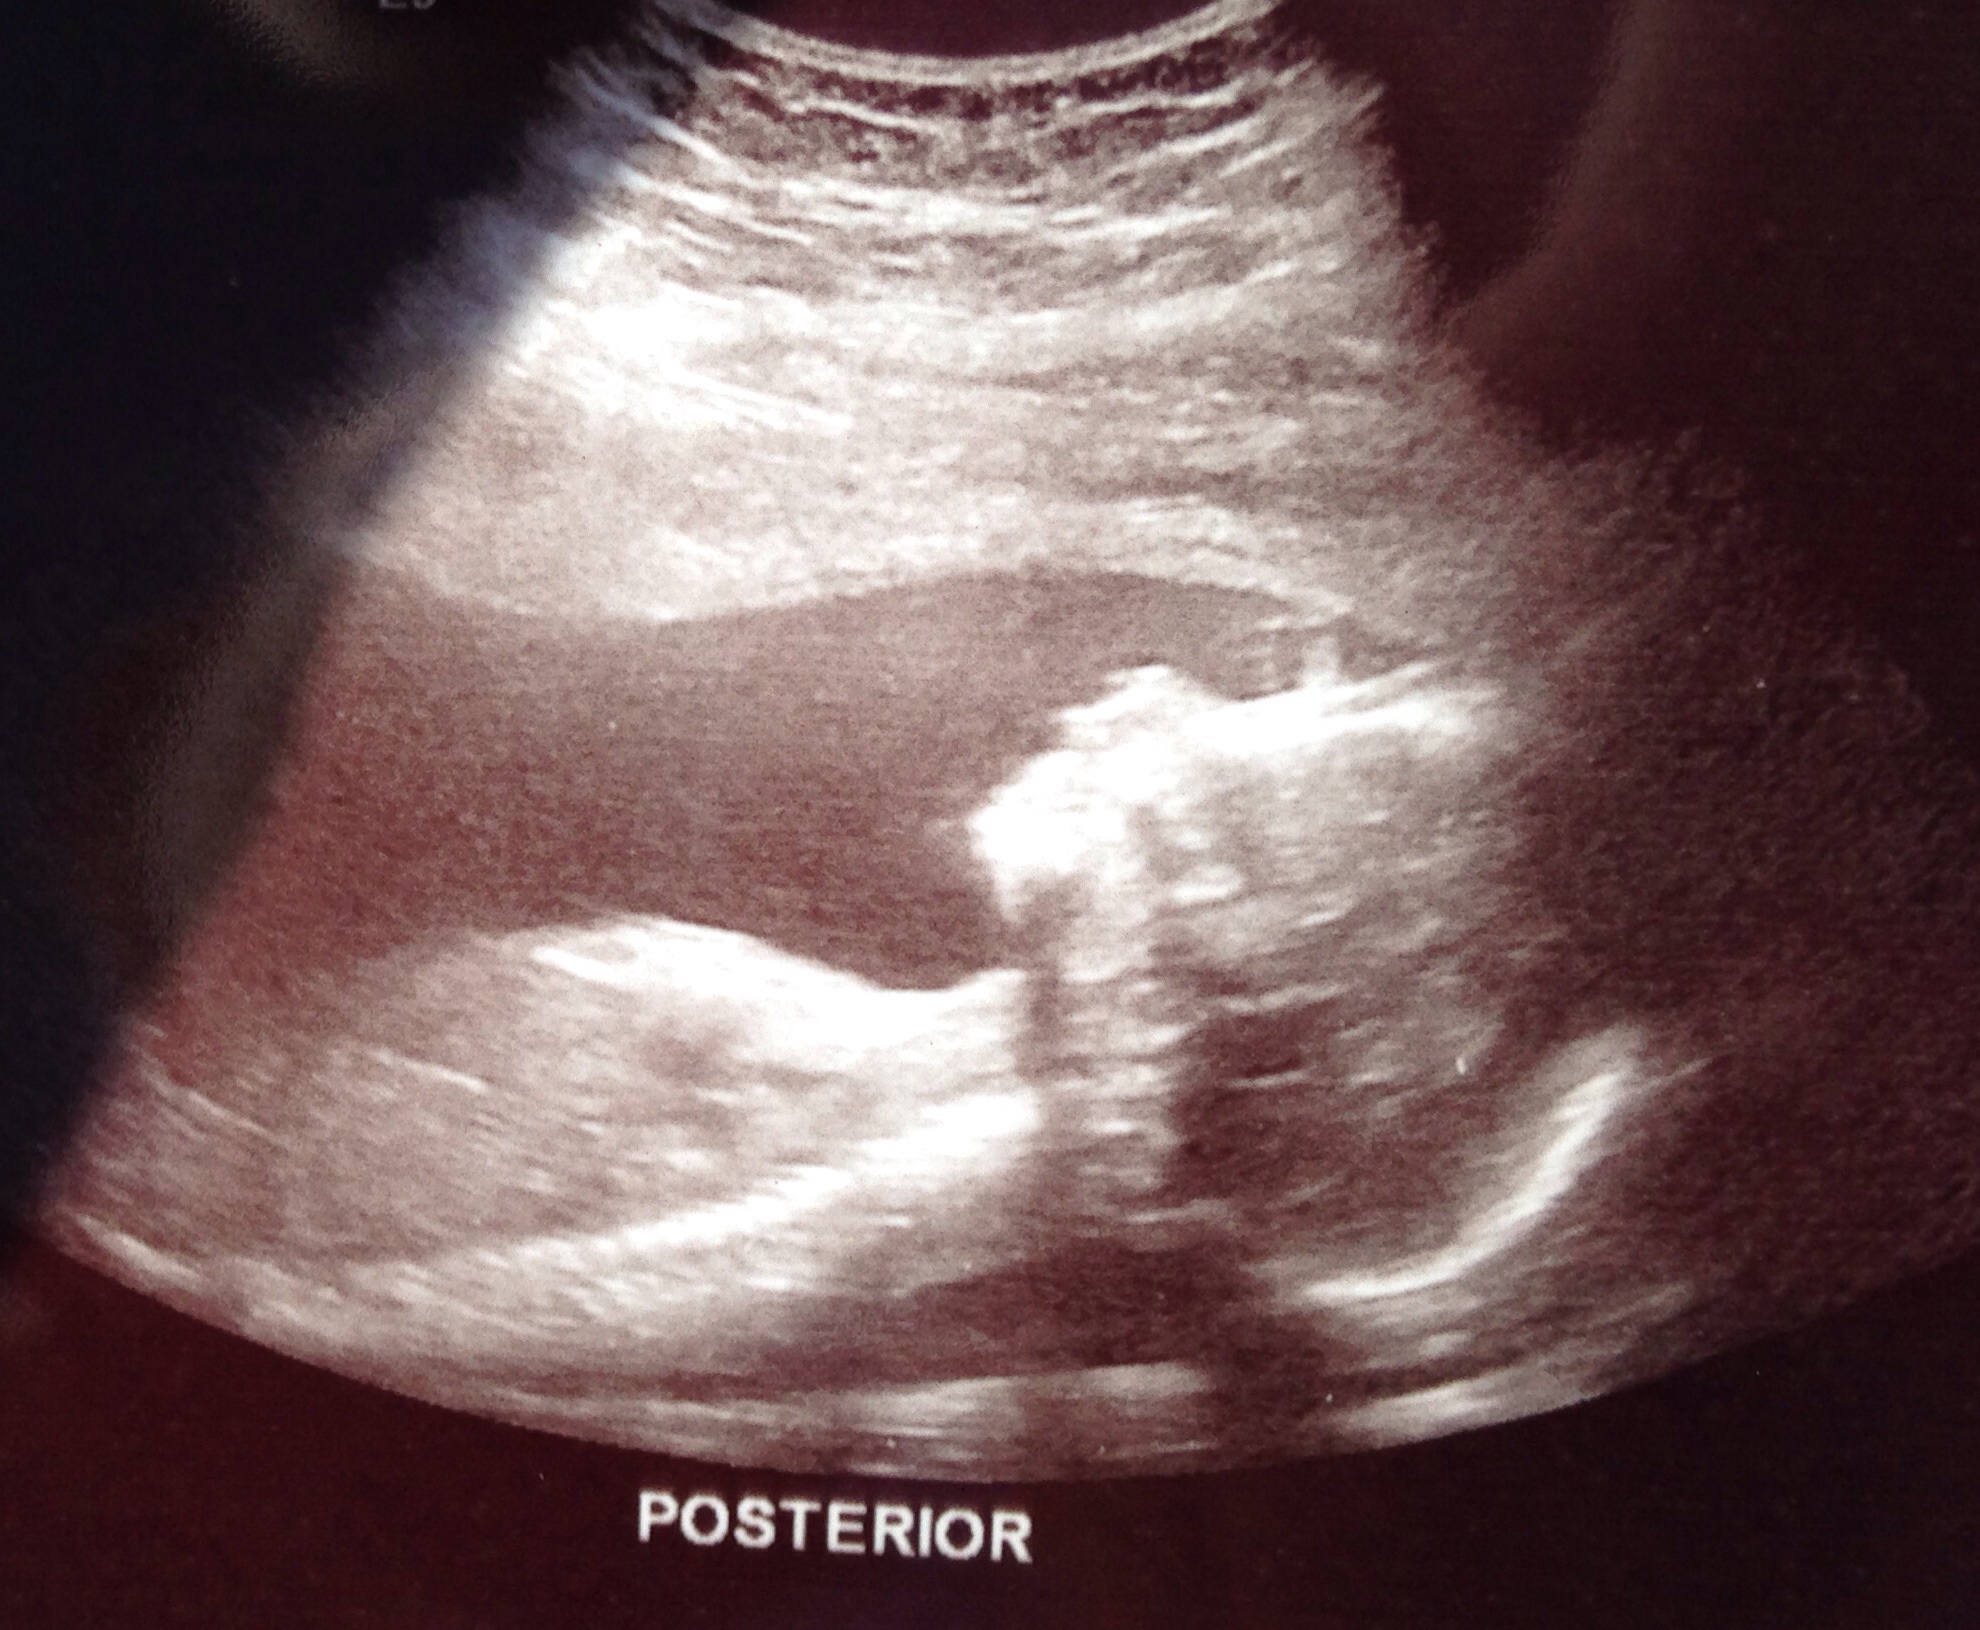

Your t's and p's worked! We have a big, stubborn, healthy baby....

BOY!!

:) over the moon! My ovarian cyst has resolved and all looks great :)

Baby G is a BOY!